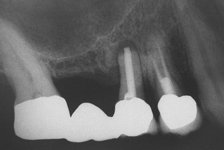

Při ztrátě molárů a premolárů v horní čelisti a jejich náhradě implantáty se často setkáváme s nedostatečnou vertikální nabídkou kosti pod čelistní dutinou, často doprovázenou i nedostatečnou horizontální nabídkou a sníženou kvalitou kosti

(v oblasti 2. premoláru v 50%, v oblasti moláru až v 80% případů nedostatečná kostní nabídka)

Od roku 1985 je tento problém řešen augmentační operací nazývanou sinus lift.

Jedná se o vyzvednutí membrány, která čelistní dutinu vystýlá, pod vyzvednutou membránou vznikne kapsa, kam se umístí augmentační materiál, do kterého se zavedou implantáty.

Vhojení implantátů se při této operaci prodlužuje na 6-12 měsíců.